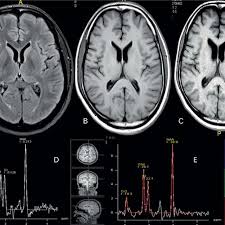

With rapid advances in computer science, AI has recently been applied to many areas including Healthcare and Life science.

Precision medicine, defined as tailored diagnosis and therapy for an individual patient, is an important emerging concept in future medicine. Imaging data is creating a path for such personalized medicine.

Thi project aim to focus on Fatel brain anomaly detection using Deep neural networks